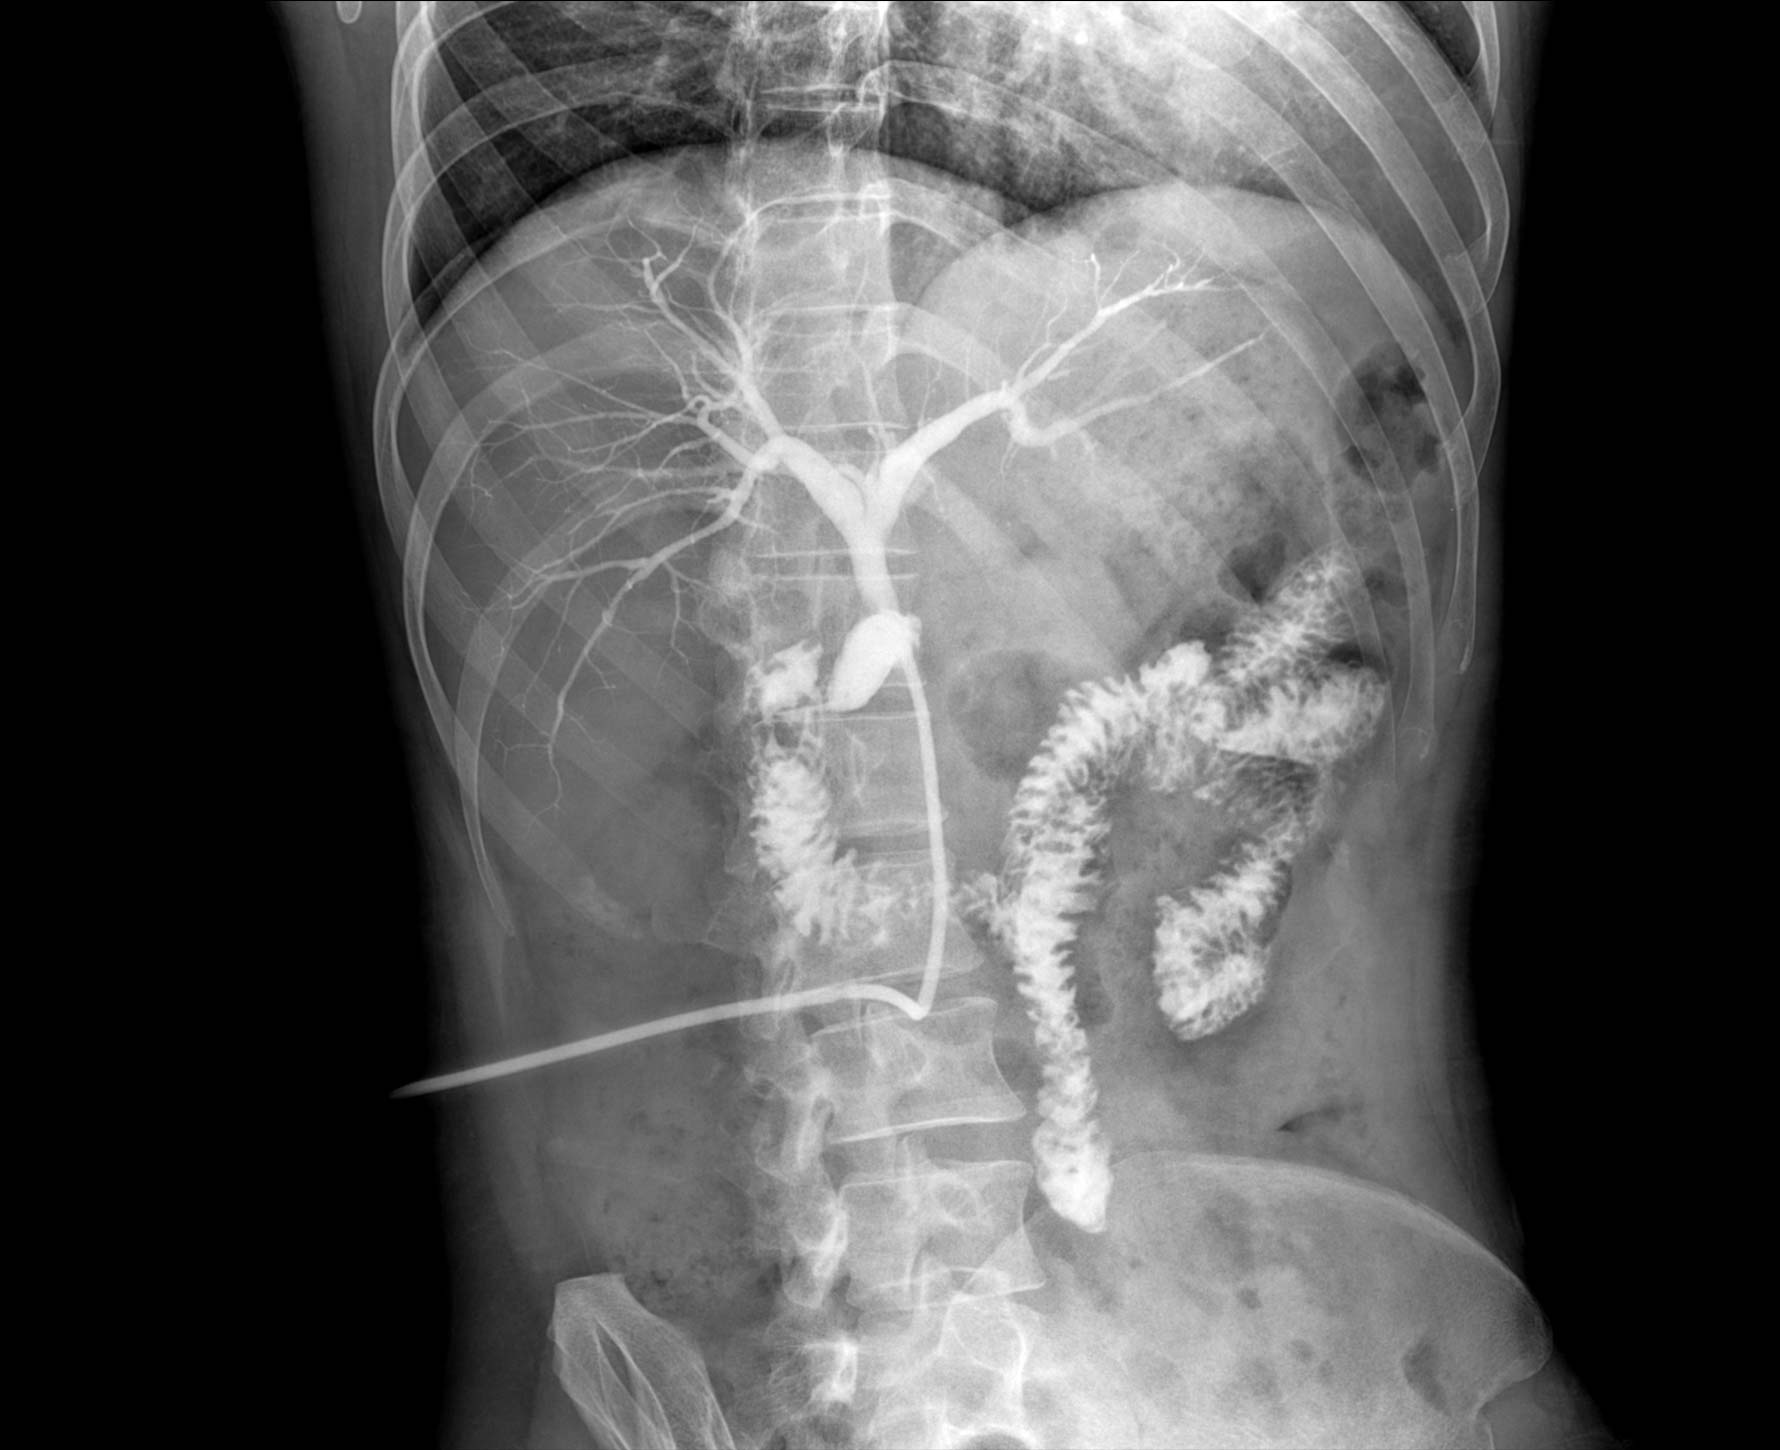

• 造影

适用于各种普通

及特殊胃肠造影检查

• 特有视频保存与回放功能

对胃肠造影检查影像实时保存,多次回放以便确定病灶部位,患者确诊好帮手,减少漏诊。

临床图像